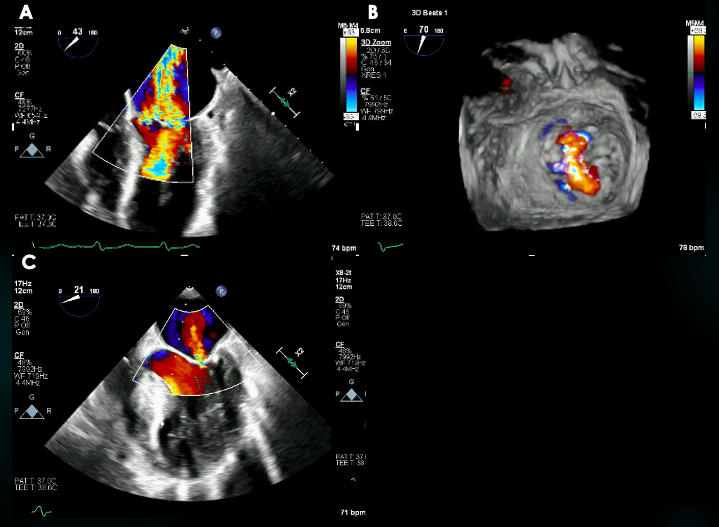

An 83-year-old woman with symptomatic severe aortic stenosis (AS) was referred for transcatheter aortic valve replacement (TAVR). Diagnostic left heart catheterization (LHC) documented diffuse 3-vessel coronary artery disease (CAD) (Videos 1-3). Transthoracic echocardiogram (TTE) showed normal biventricular function, severe AS, and minimal mitral regurgitation (MR) (Figure 1A and B; Video 4). The Heart Team deemed that she was at high/prohibitive surgical risk given multiple comorbidities and frailty.

The patient underwent transfemoral TAVR with a 25-mm Navitor valve (Abbott) after initial ballon aortic valvuloplasty (BAV). TTE and angiography documented normal valve positioning and function, and normal coronary perfusion. Within a few minutes of the deployment of the valve, the patient developed persistent hypotension and vasopressors were initiated. TTE showed anteroseptal hypokinesis and severe MR with a centrally directed jet (Figure 1C and D; Video 5). The patient was intubated, and transesophageal echocardiogram (TEE) confirmed severe MR with a broad, centrally directed jet from poor mitral leaflet coaptation (Figure 2A and B; Videos 6 and 7). A diagnostic left heart cardiac catheterization showed no changes in the underlying CAD. An intra-aortic balloon pump was placed, and TEE showed MR improvement from severe to mild (Figure 2C; Video 8). The patient was moved to the cardiac intensive care unit for continuous hemodynamic monitoring. Her clinical course progressively improved and she was discharged home on post-procedure day 7 in stable condition.